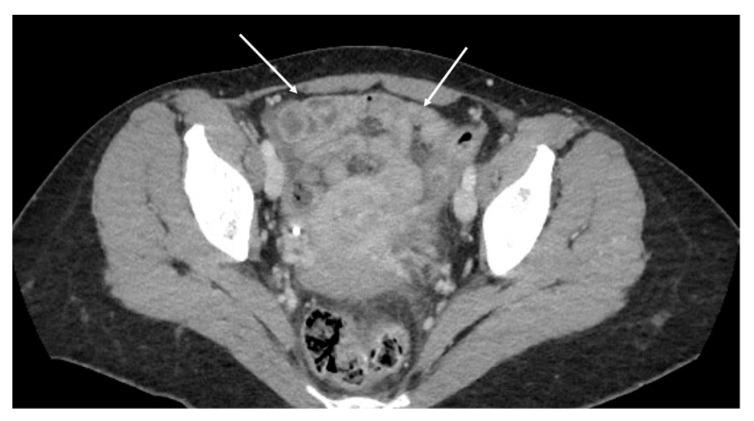

Peritoneal carcinosis is a condition characterized by the spread of cancer cells to the peritoneum, which is the thin membrane that lines the abdominal cavity. It is a serious condition that can result from many different types of cancer, including ovarian, colon, stomach, pancreatic, and appendix cancer. The diagnosis and quantification of lesions in peritoneal carcinosis are critical in the management of patients with the condition, and imaging plays a central role in this process. Radiologists play a vital role in the multidisciplinary management of patients with peritoneal carcinosis. They need to have a thorough understanding of the pathophysiology of the condition, the underlying neoplasms, and the typical imaging findings. In addition, they need to be aware of the differential diagnoses and the advantages and disadvantages of the various imaging methods available. Imaging plays a central role in the diagnosis and quantification of lesions, and radiologists play a critical role in this process. Ultrasound, computed tomography, magnetic resonance, and PET/CT scans are used to diagnose peritoneal carcinosis. Each imaging procedure has advantages and disadvantages, and particular imaging techniques are recommended based on patient conditions. Our aim is to provide knowledge to radiologists regarding appropriate techniques, imaging findings, differential diagnoses, and treatment options. With the advent of AI in oncology, the future of precision medicine appears promising, and the interconnection between structured reporting and AI is likely to improve diagnostic accuracy and treatment outcomes for patients with peritoneal carcinosis.

腹膜癌是一种以癌细胞扩散至腹膜为特征的病症,腹膜是衬于腹腔的一层薄膜。它是一种严重的病症,可由多种不同类型的癌症引发,包括卵巢癌、结肠癌、胃癌、胰腺癌和阑尾癌。腹膜癌中病变的诊断和定量对于该病症患者的管理至关重要,而影像学在这一过程中发挥着核心作用。放射科医生在腹膜癌患者的多学科管理中起着至关重要的作用。他们需要对该病症的病理生理学、潜在肿瘤以及典型的影像学表现有透彻的了解。此外,他们需要知晓鉴别诊断以及各种可用影像学方法的优缺点。影像学在病变的诊断和定量中起着核心作用,放射科医生在这一过程中起着关键作用。超声、计算机断层扫描、磁共振成像和正电子发射断层显像/计算机断层扫描(PET/CT)用于诊断腹膜癌。每种成像检查都有其优缺点,会根据患者情况推荐特定的成像技术。我们的目的是向放射科医生提供有关合适技术、影像学表现、鉴别诊断和治疗方案的知识。随着人工智能在肿瘤学中的出现,精准医学的未来似乎很有前景,结构化报告与人工智能之间的相互联系可能会提高腹膜癌患者的诊断准确性和治疗效果。